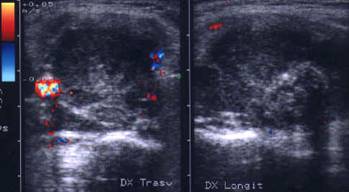

Lob drept , proiectie longitudinala si trasversala .

Barbat de 44 ani. Nodul mare in lobul drept si istm de 31x44x44mm, (30 cc) cu contur net, hipoecogen, neomogen, cu macrocalcificare.

Examn citologic: neoplazie oncocitara (a c. Hurthle).

Examen histologic postoperator: adenom cu celule Hurthle.